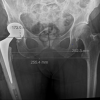

Six weeks into rehabilitation, during one of the mobilization sessions, the patient reported pain at the site of prophylactic nailing in the right femur. Radiographs revealed a minimally displaced fracture in the proximal third of the right femur (Fig. 6). Conservative management was pursued due to the absence of significant displacement or angulation, which was probably due to the prophylactic nail in situ. Mobilization was restricted to bedside exercises for 6 weeks, followed by a gradual return to full weight-bearing activity. There was no complaint of worsening of pain or any other symptoms with this conservative approach. With regular clinical and radiological follow-ups, the patient demonstrated progressive healing, transitioning to single crutch-assisted ambulation by 6 months. One-year post-surgery, complete bilateral fracture consolidation was observed (Fig. 7), and the patient achieved unaided, pain-free mobility. She is still under follow-up and is doing well, with no further symptoms so far.